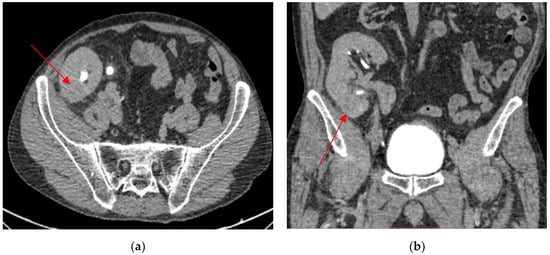

2. Case Presentation